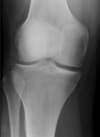

Les examens complémentaires du genou

Les examens complémentaires commencent traditionnellement par une radiographie du genou dans le but d'éliminer des lésions associées comme des fractures ostéochondrales. Mais la radiographie ne met pas en évidence les ligaments.

L'échographie permet aussi de visualiser les ligaments du genou mais pour les ligaments croisés, c'est assez complexe.

L'IRM est l'examen de choix pour mettre en évidence une atteinte des ligaments notamment des croisés. Il ne doit jamais être prescrit en première intention !